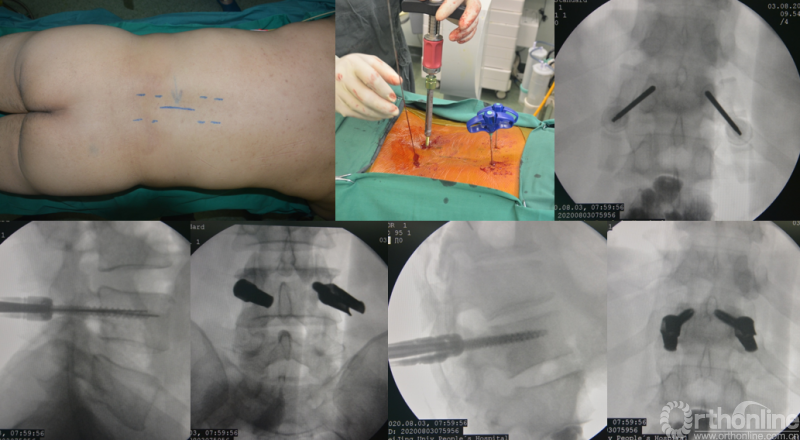

为进一步减少创伤,获得更好的综合疗效。骨采用经皮内固定的微创杂交技术,暨经皮内固定结合小切口分离手术,手术失血900ml,术后7天出院。

术中资料

手术视频:http://res.orthonline.com.cn/video/SSZH.mp4